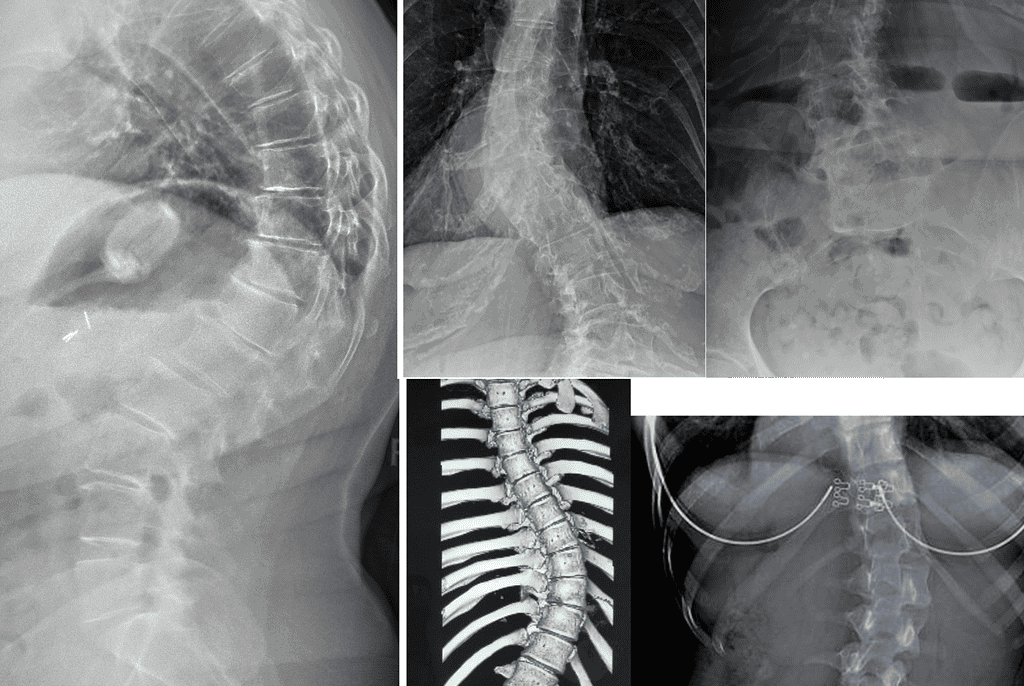

Measurable outcomes on X-ray. Here is what our co-managed patients have experienced.

Note: Individual results vary. All measurements taken on calibrated standing AP radiographs by the treating doctor. Cases shown with patient/guardian consent.

In-Brace Correction is normally 48% but we could see 63%.*

Out-of-Brace curves achieved 37.60% improvement if their curves are 20°-40°.

Results: curve correction: 76.9%, curve stabilization: 23.1%, curve progression 0%